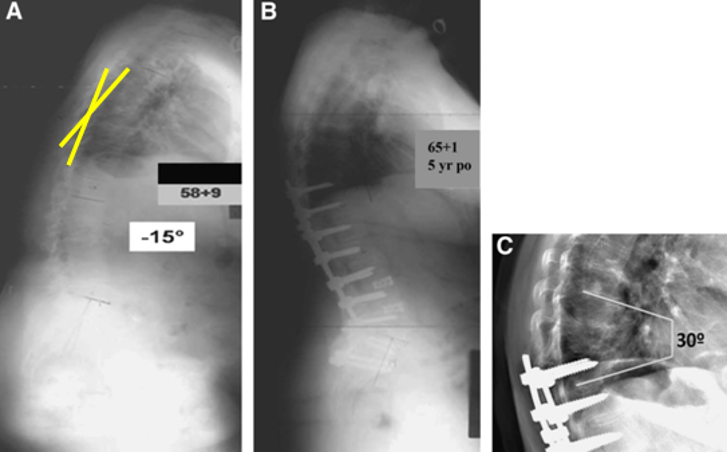

T10骨盆固定,出现交界性后凸

行翻修手术:T9/10SP截骨,延长到T4固定,预防性双侧肋骨固定(VEPTR)

图32-33 肋骨固定

(4)Topping-Off 技术

Topping-off技术又称为融合区+上位邻近节段动态稳定技术

即从融合节段向活动节段过度的手术,旨在融合节段和活动节段之间形成缓冲区,降低邻近节段应力集中

图34-35 据文献报道,可应用一种环形和夹层胶带的技术,以重新创建一个有机后张力带UIV和UIV+1之间将上下棘突绑扎后,增强交界区后方张力带结构强度